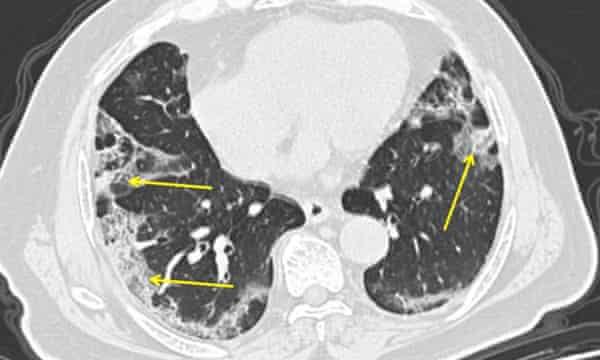

Solunumları hızlanmış olmakla beraber görünümleri akciğer röntgenindeki berbat pnömoni ve çok düşük oksijen seviyelerine göre çok fazla sıkıntılı değildi.

Kovid pnömonisinde enflamasyon ile hava kesecikleri sönmeye ve oksijen düşmeye başlıyor, oysa akciğerler henüz esnekliğini kaybetmiş veya sıvı ile dolmuş değildir. Bu, hastalar hâlâ karbon dioksidi atabiliyor demektir ve karbon dioksit yükselmediği için de nefes darlığı yoktur.

Kovid pnömonilerinin yüzde 20’ sinde akciğer hasarının ikinci ve daha ölümcül dönemi başlar. Akciğerlerde sıvı birikir, akciğerler sertleşir, karbon dioksit yükselir ve hasta solunum yetersizliğine girer.